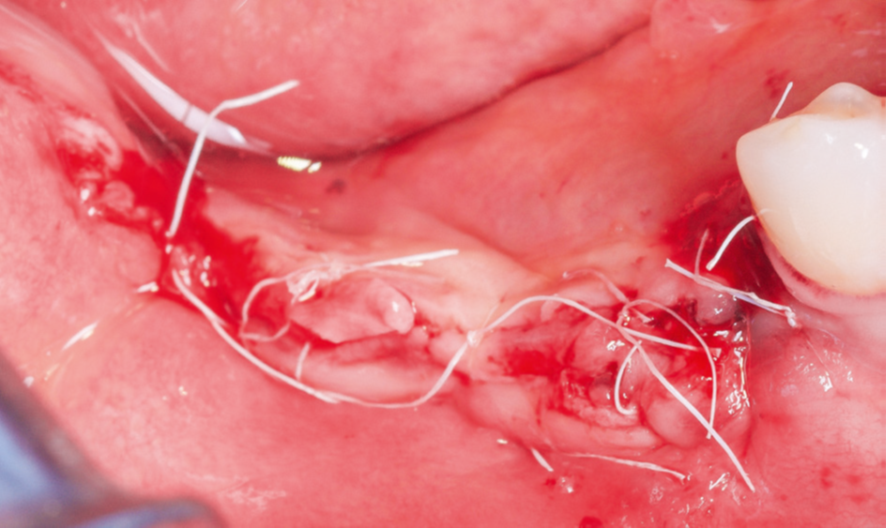

Após a maturação do tecido gengival, procedeu-se ao preparodo leito receptor com incisão e descolamento mucoperiosteal,liberando-se o tecido lingual por meio do alívio da tensão musculardo milo-hióideo (Figura 3) com o descolador de Molt (Supremo Instrumentais). Em seguida, prosseguiu-se com a coleta de osso autógeno do ramo mandibular (área próxima ao leito receptor, do mesmo lado, conforme Figura 4). As lâminas ósseas foram adaptadas e fixadas nas corticais vestibular e lingual com parafusos de titânio (Orth – Implacil Osstem / Figura 5), criando um compartimento do tipo caixa, preenchendo-se o seu interior com osso particulado autógeno (Figura 6). A sutura foi realizada com pontos em colchoeiro horizontal seguidos de pontos simples interrompidos (Figura 7). A cicatrização foi considerada satisfatória.